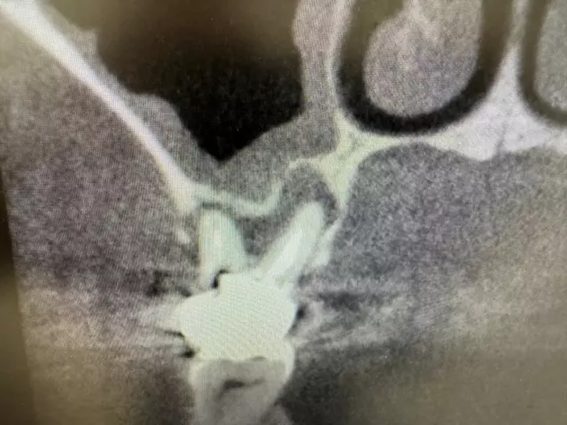

| 主訴 | インプラント 左上6番7番部 インプラント埋入 |

| 治療内容 | 左上6番7番部インプラント埋入。 左上6番部 上顎洞まで約1.5㎜。 左上6番 抜歯即時埋入。 左上7番 もともと歯が無かったため、通常埋入。 |

上顎洞へ突き抜けているように見えますが、抜歯窩への埋入のため、実際は抜けていません。